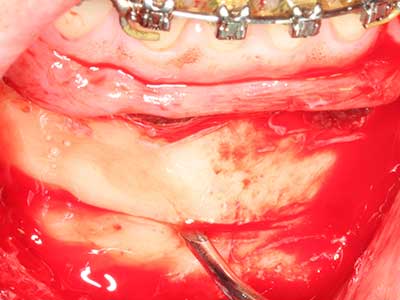

En la extracción de bloques óseos la piezocirugía también presenta ventajas adicionales: Además de la alta precisión en la osteotomía que ya se ha descrito antes, se ha comprobado que el uso de los delgados insertos de sierra resulta especialmente cuidadosas con el hueso. Frente a esto, sobre todo cuando se usan las fresas de Lindemann, cabe esperar pérdidas en la extracción significativamente más altas debido al mayor grosor de la parte frontal del cabezal (Lakshmiganthan, Gokulanathan et al. 2012). La separación basal que se necesita en particular en los injertos de bloque extraídos de forma retromolar se ve facilitada mediante sierras perpendiculares especialmente previstas a tal fin, lo que permite considerar que la cirugía piezoeléctrica es un procedimiento preciso y seguro para la obtención de bloques de hueso en el área retromolar (Happe 2007) (fig. 1-12).

Aplicación: Partición ósea / Cortical Split

El tejido óseo no solo tiene un contenido puramente mineral, sino que también presenta una importante proporción de fibras de colágeno. Esto no solo garantiza una buena resistencia a la presión, sino también una cierta flexibilidad, que puede aprovecharse para la realización de aumentos. En la plastia de expansión clásica a efectos de una partición ósea, la cresta maxilar atrofiada se divide en su eje longitudinal y, tras alcanzar una profundidad de osteotomía suficiente, se extiende con cuidado (fig. 13-16), en un caso ideal sin desperiostizar de forma visible el maxilar (Brugnami, Caiazzo et al. 2014, Stricker, Fleiner et al. 2014). Los sistemas de tornillos y placas con distancia de expansión creciente han demostrado su eficacia para distanciar entre sí las dos tablas óseas por debajo del umbral de rotura. Por regla general, se requieren anchuras de hueso residual de al menos 3 a 4 mm (Chiapasco, Zaniboni et al. 2006) para garantizar una flexibilidad y una cobertura ósea suficientes de los implantes que van a incorporarse. En caso necesario, una osteotomía de descarga vertical unilateral o bilateral puede mejorar la flexibilidad. Como alternativa a la técnica clásica se ha descrito una combinación con otras técnicas de aumento, sobre todo en la parte bucal.

Con el uso de sierras piezoeléctricas la división se efectúa de forma especialmente cuidadosa y sin pérdidas importantes de las dimensiones, por lo que no se han encontrado diferencias significativas entre los implantes realizados en el maxilar dividido y en la cresta alveolar no deficitaria (Chiapasco, Zaniboni et al. 2006, Danza, Guidi et al. 2009). No obstante, precisamente en la partición profunda y limitada de forma local, es preciso asegurarse de que exista una adecuada irrigación por agua para evitar que se produzcan sobrecargas térmicas en las áreas de osteotomía apical.